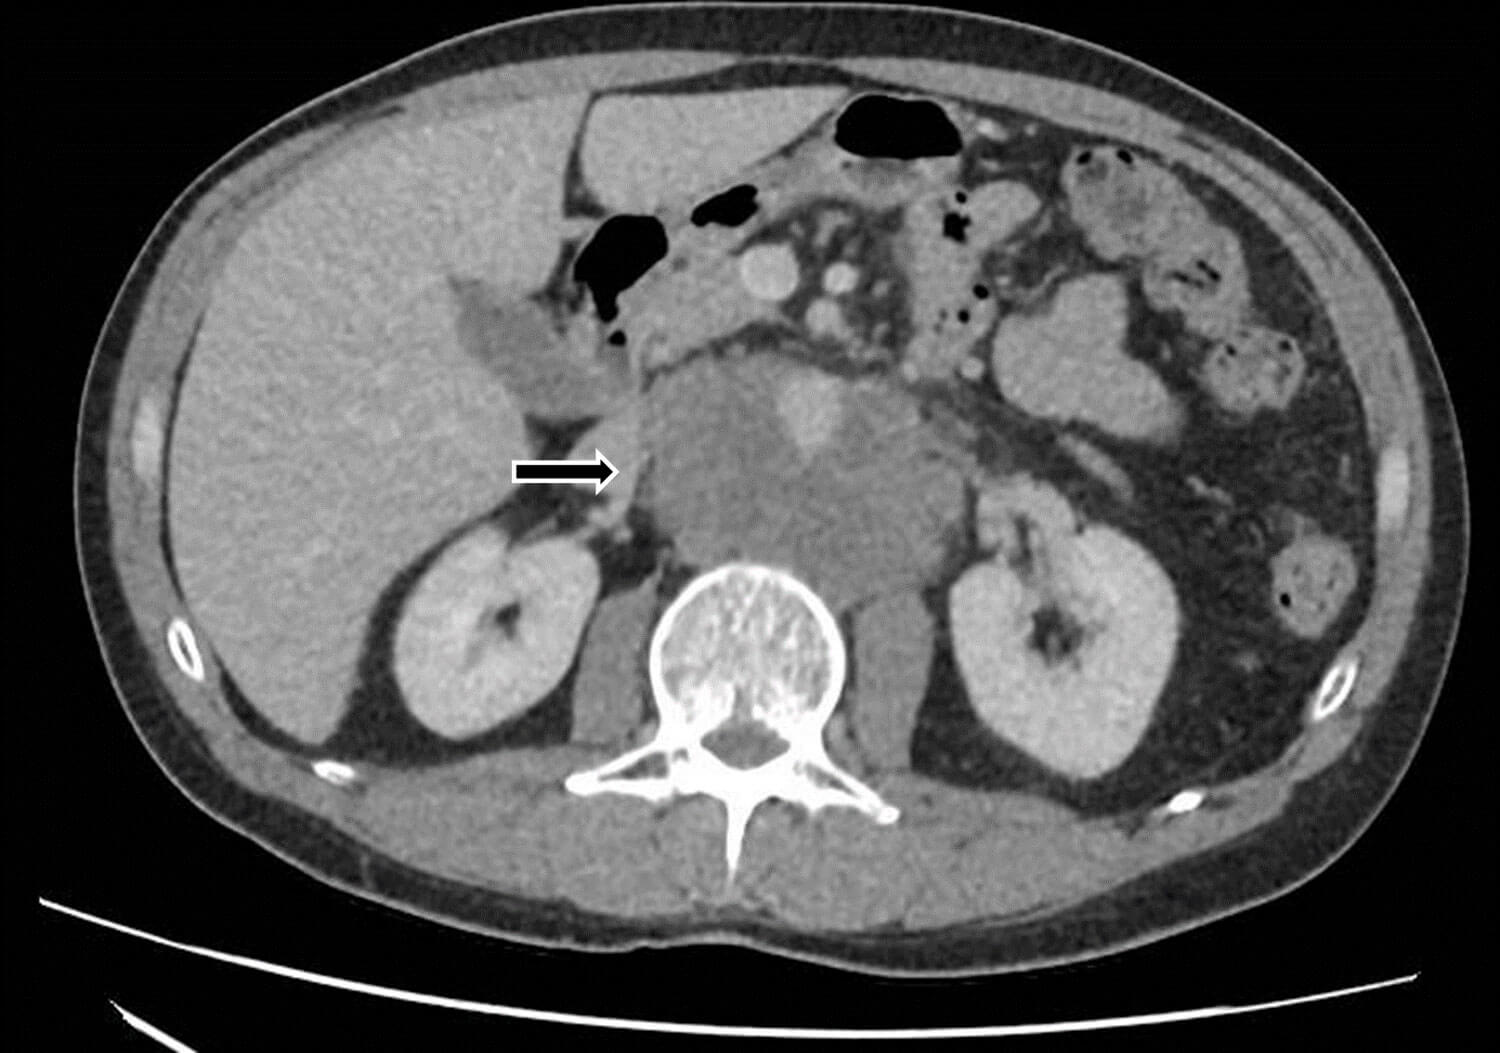

A 43-year-old man attended his GP with a three month history of worsening abdominal and back pain. An ultrasound (US) of the abdomen showed prominent para-aortic lymph nodes and he was referred under the two-week-wait for suspected cancer of unknown primary. A CT abdomen and pelvis demonstrated a large conglomerate retroperitoneal mass, suspicious for lymphoma, as well as a large pulmonary embolus (Figure 1).

Figure 1: Large retroperitoneal mass extending to the common iliac vessels.